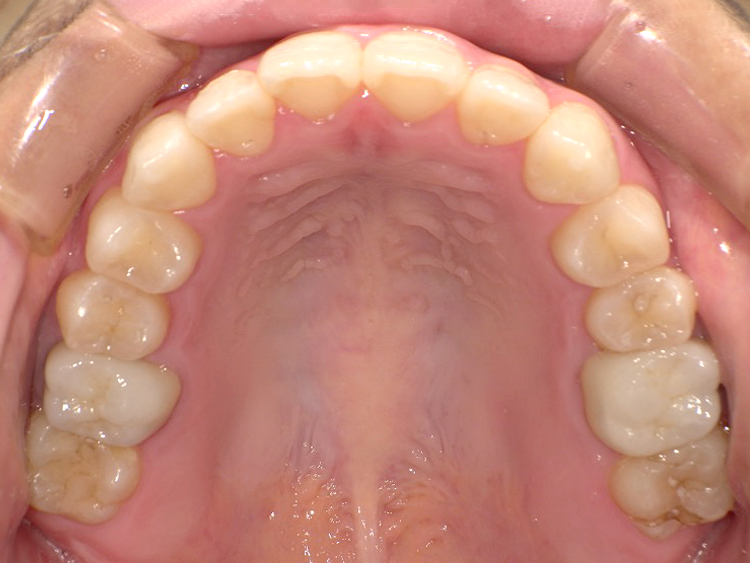

症例5

Before

After

| 主訴 | 上下3-3の並びが気になる |

|---|---|

| 年齢 | --- |

| 治療 期間 |

約1年 |

| 治療 内容 |

インビザライン5-5 |

| 治療費 | ¥517,000(税込)/調整料含む |

| 治療のリスク | 奥歯を動かさないので、前に出して並べていく。 歯と歯が移動するスペースを作るので、知覚過敏の症状がまれにでる。 歯を動かすことで、歯茎が下がるリスクある。 矯正終了後は、リテーナーを使用し、後戻りを防ぐ必要がある。 |